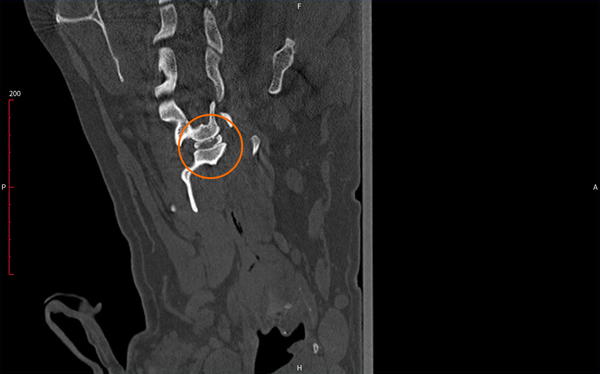

Hình ảnh chụp CT-scan sau phẫu thuật

Kết quả sau phẫu thuật

Chỉ sau vài ngày, chức năng vận động của Maxi đã cải thiện rõ rệt, cho thấy tủy sống và dây thần kinh được giải phóng thành công.

Đây là một dấu hiệu phục hồi tích cực, khẳng định hiệu quả của phẫu thuật thoát vị đĩa đệm ở chó khi được thực hiện đúng kỹ thuật và kịp thời.